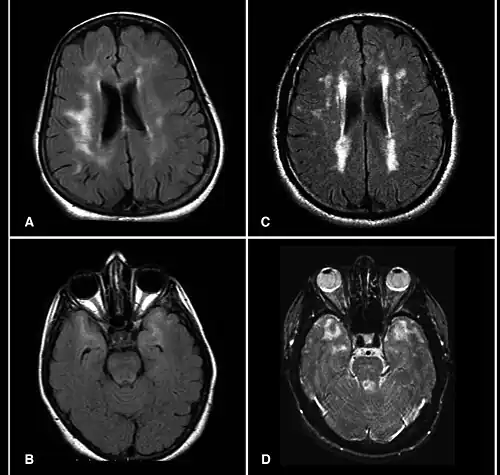

| Brain MRI from patients with CADASIL showing multiple lesions. | |

MRIs show hypointensities on T1-weighted images and hyperintensities on T2-weighted images, usually multiple confluent white matter lesions of various sizes, are characteristic. These lesions are concentrated around the basal ganglia, peri-ventricular white matter and the pons and are similar to those seen in Binswanger disease.[2][11] These white matter lesions are also seen in asymptomatic individuals with the mutated gene.[12] While MRI is not used to diagnose CADASIL, it can show the progression of white matter changes even decades before onset of symptoms.